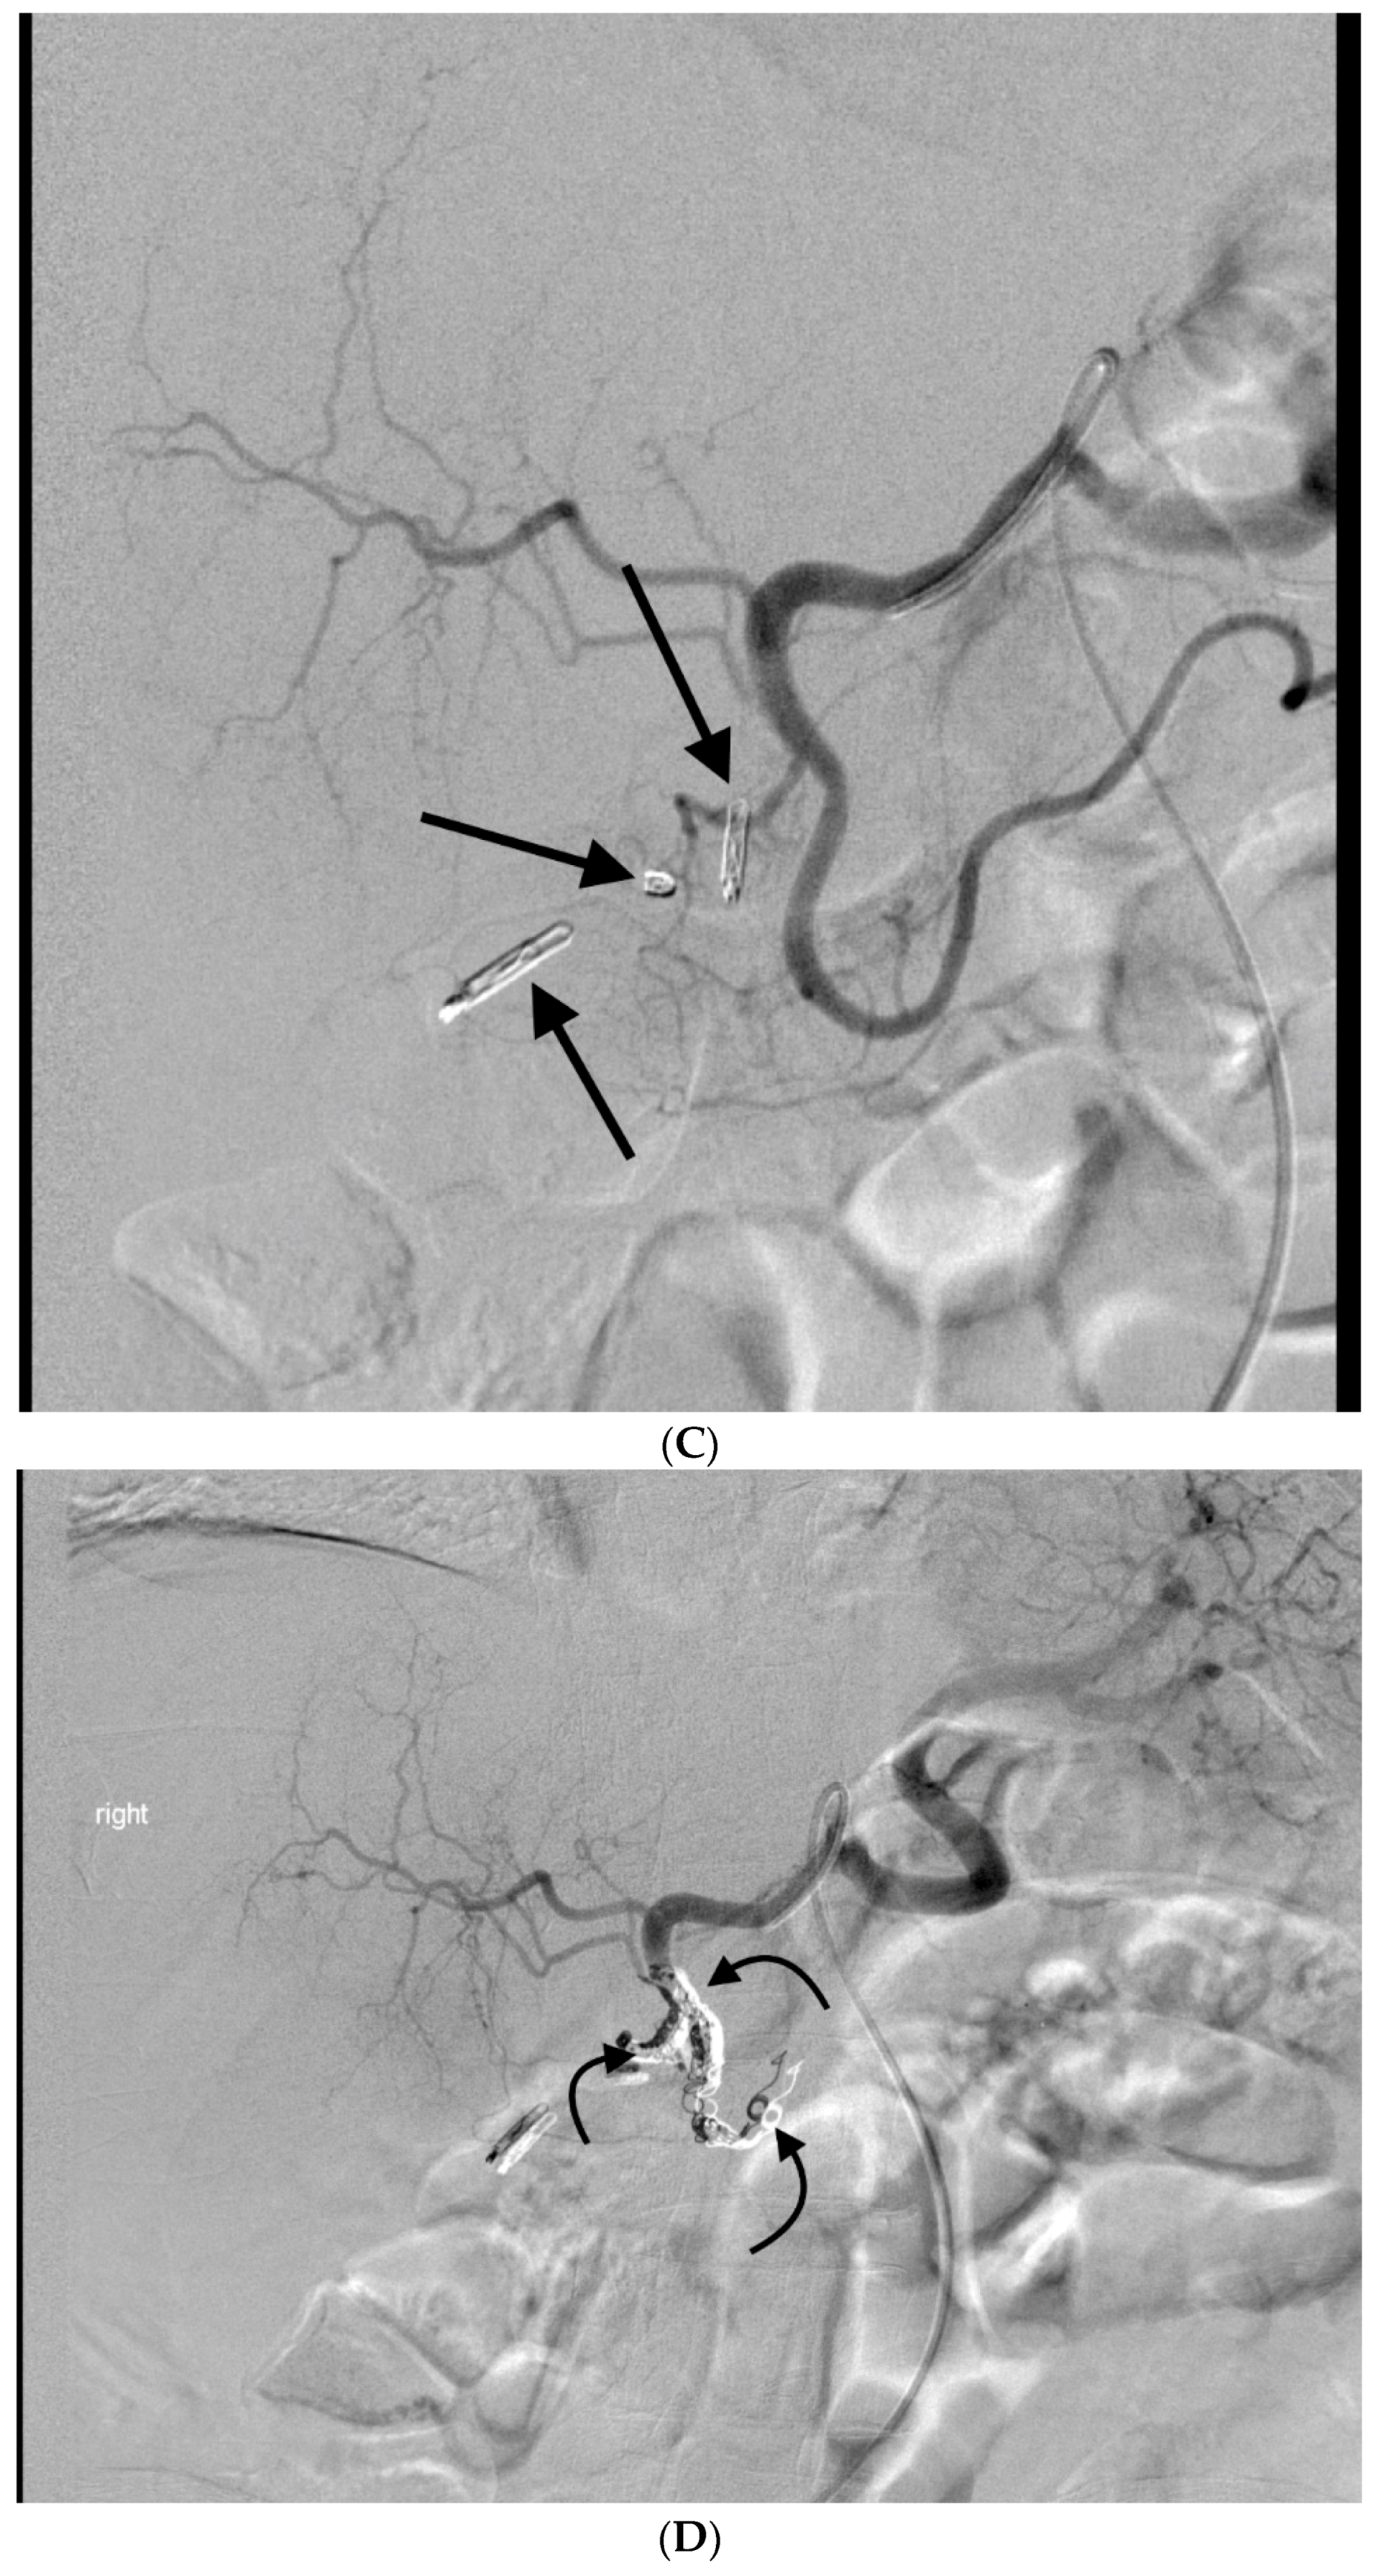

3. GDA Embolization in Gastrointestinal Bleeding